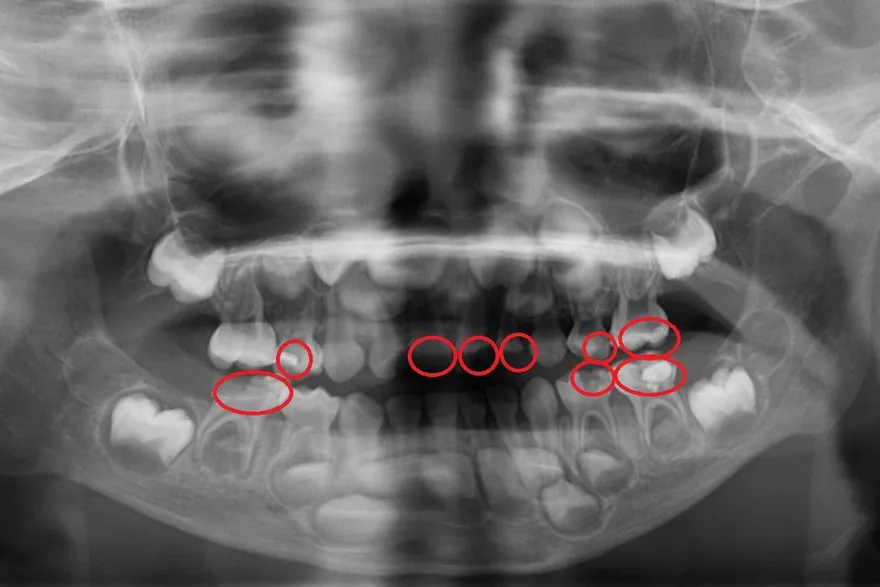

學校塗氟非萬靈丹!5歲童蛀牙惡化成蜂窩性組織炎

齲齒

蜂窩性組織炎

乳牙

口腔保健

塗氟

口腔檢查

台北慈濟醫院